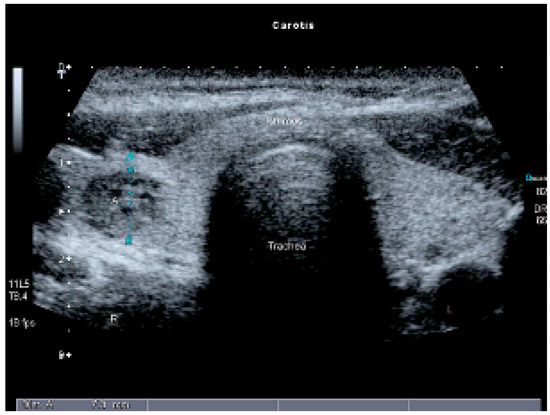

Interesting Images

Autonomes Schilddrüsenadenom und Angiosonographie

by Michel Zuber and Lukas Frey

Cardiovasc. Med. 2006, 9(10), 361; https://doi.org/10.4414/cvm.2006.01204 - 27 Oct 2006

Viewed by 59

Abstract

Eine 56jährige Patientin sucht den Hausarzt auf wegen total globaler Amnesie [...] Full article

Show Figures

Figure 1